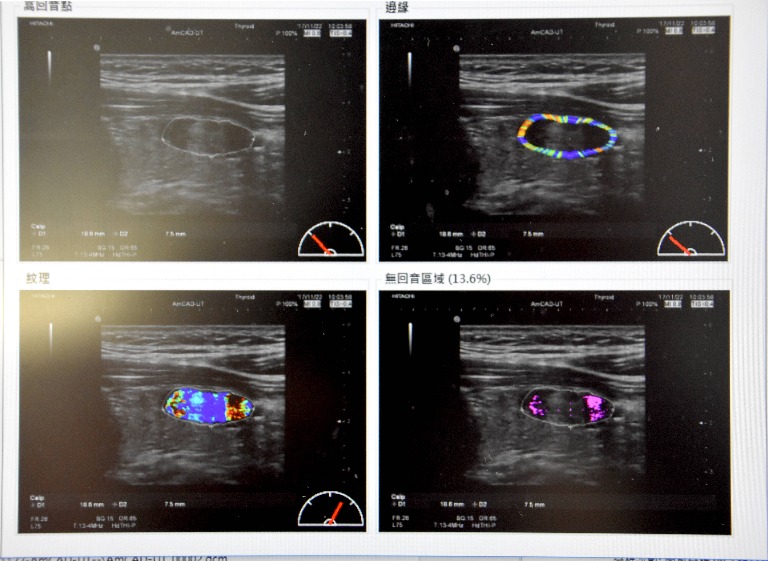

甲狀腺結節利用超音波影像診斷,近來也有甲狀腺超音波電腦輔助系統作為輔助工具,在超音波影像上圈選出結節的大小,便可擷取結節特徵,並且讓超音波黑白影像變成彩色的,更方便醫師判讀,由於無侵入性,也便於患者作為長期追蹤的新選擇。